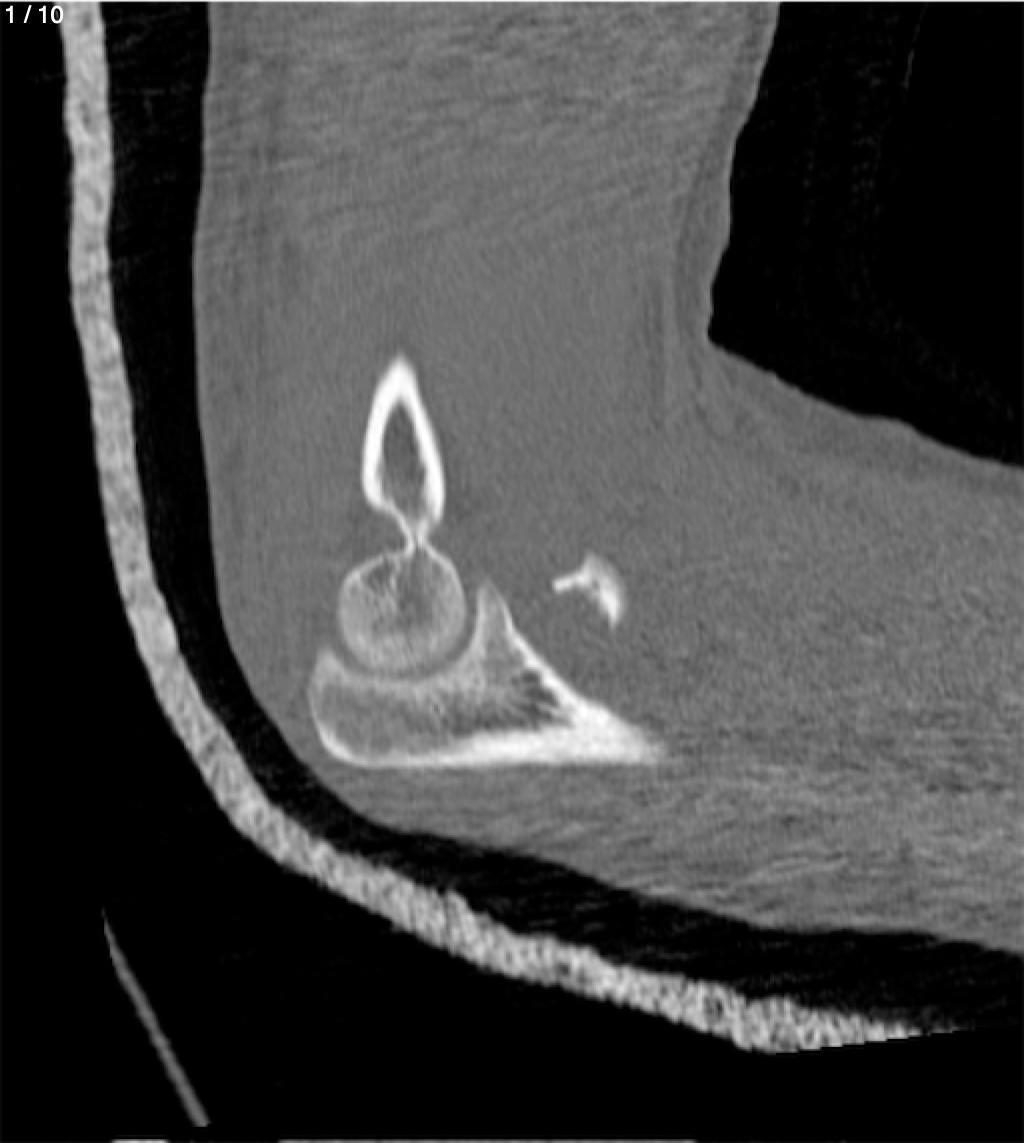

Antonio Dominguez Tino 21 A - Tac Codo Izq